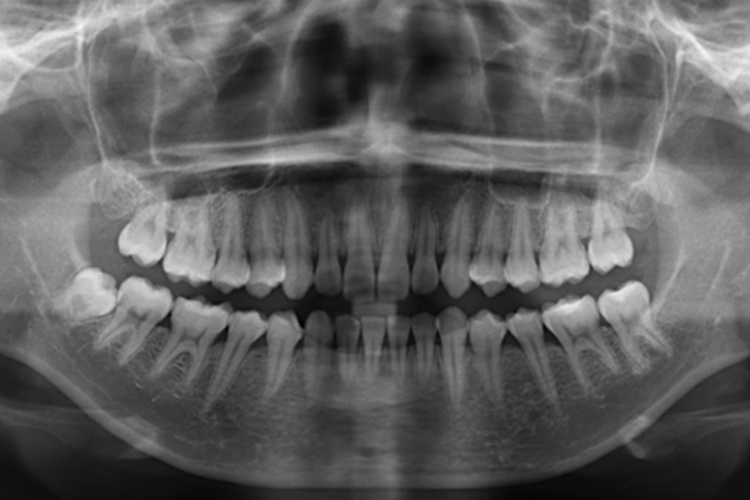

正常牙齿拍片结果显示牙齿排列整齐、上下颌牙的咬合关系正常,可有轻微的错(牙合)畸形,但不影响生理功能。

正常牙齿拍片可以显示出口腔内牙齿的形态,表现为牙齿排列整齐、上下颌牙的咬合关系正常。部分情况下可表现出轻微的错(牙合)畸形,但不影响生理功能,也属于正常的牙齿状态。